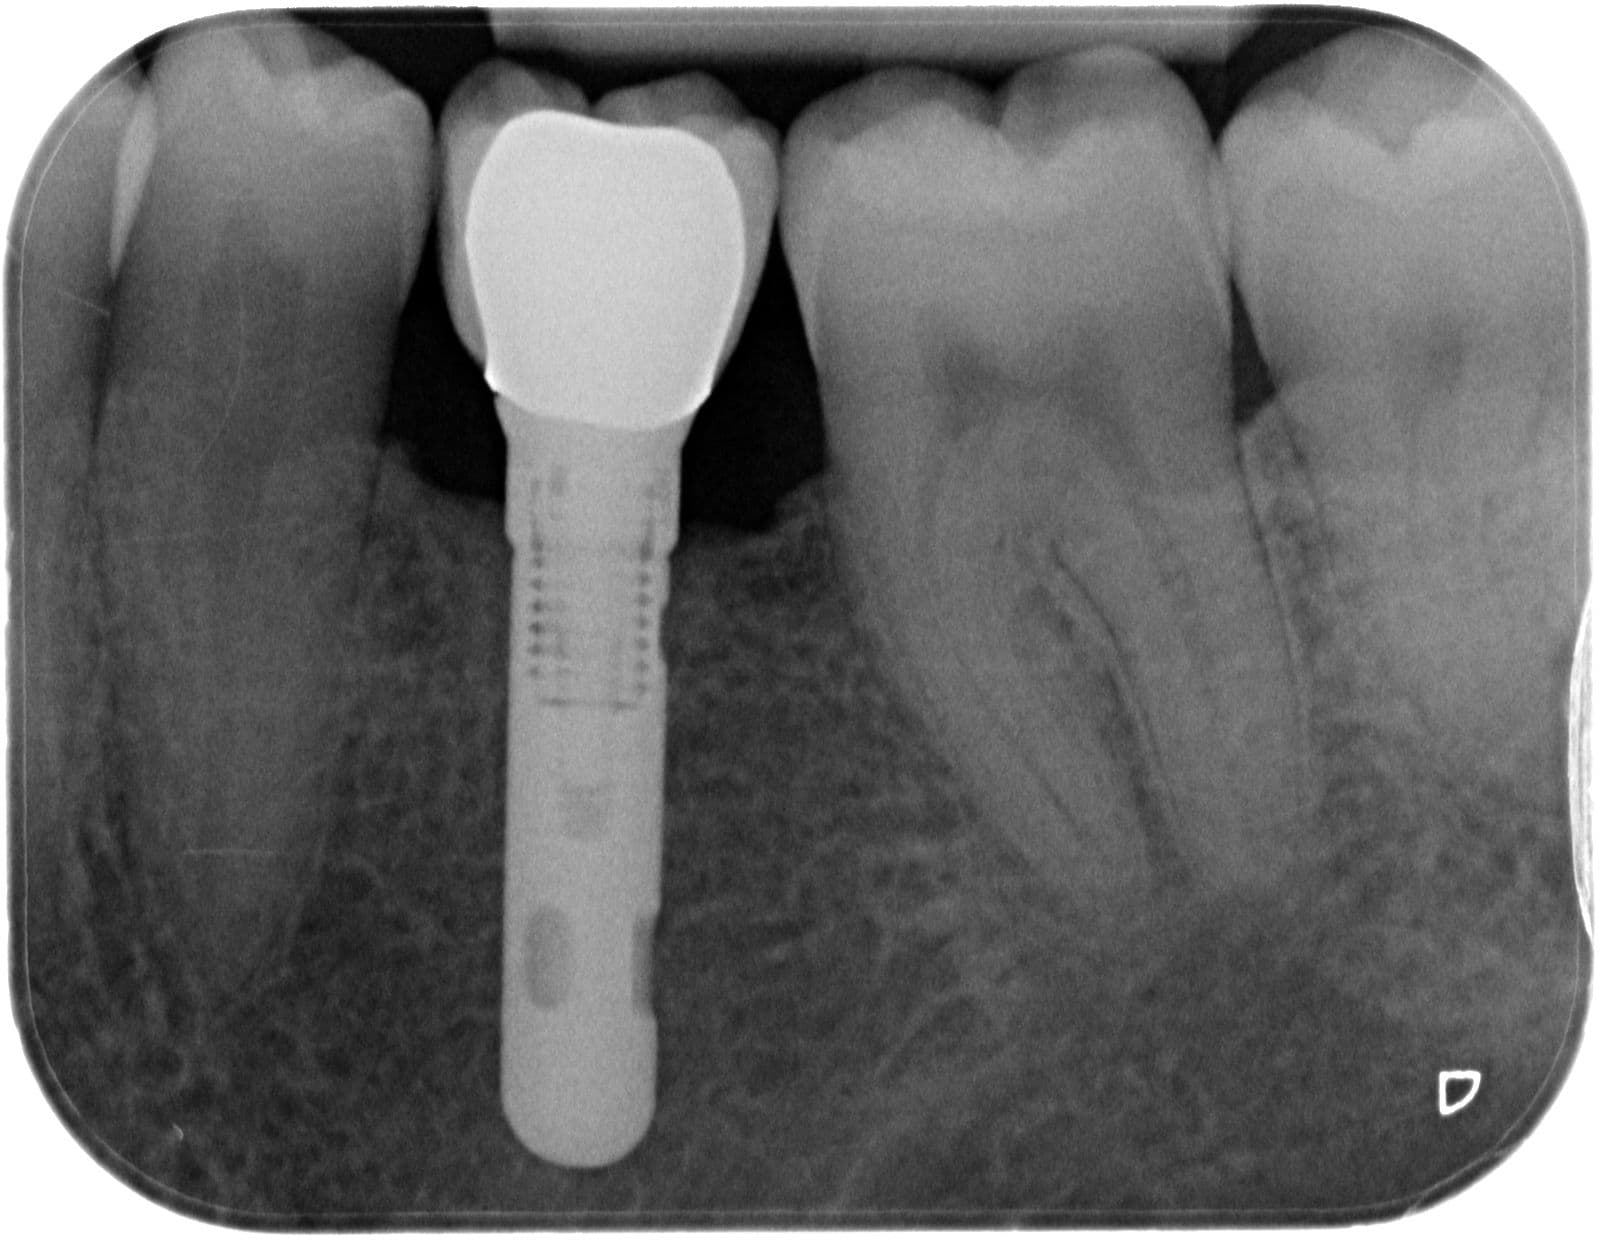

Durch die moderne Implantologie werden „künstliche Zahnwurzeln“ in den Kieferknochen eingepflanzt. Sie bieten Kronen, Brücken oder Prothesen festen Halt. So können Lücken ohne Verletzung gesunder Nachbarzähne geschlossen werden oder Sie können mit einer fest verankerten Prothese wieder kraftvoll zubeißen.

Bewährt haben sich dabei Titanimplantate, bei Implantaten im Frontzahnbereich können auch Keramikimplantate zum Einsatz kommen.

Der Weg zu Ihren „neuen Zahnwurzeln“ führt normalerweise über zwei Eingriffe: zuerst werden die Implantate in Ihren Kiefer eingesetzt und nach zwei bis fünf Monaten erfolgt die Freilegung, ein kleiner Eingriff, bei dem das Zahnfleisch über den Implantaten eröffnet wird. Danach kann die Herstellung des Zahnersatzes beginnen. In Ausnahmefällen kann ein Implantat auch sofort mit Zahnersatz versorgt werden.